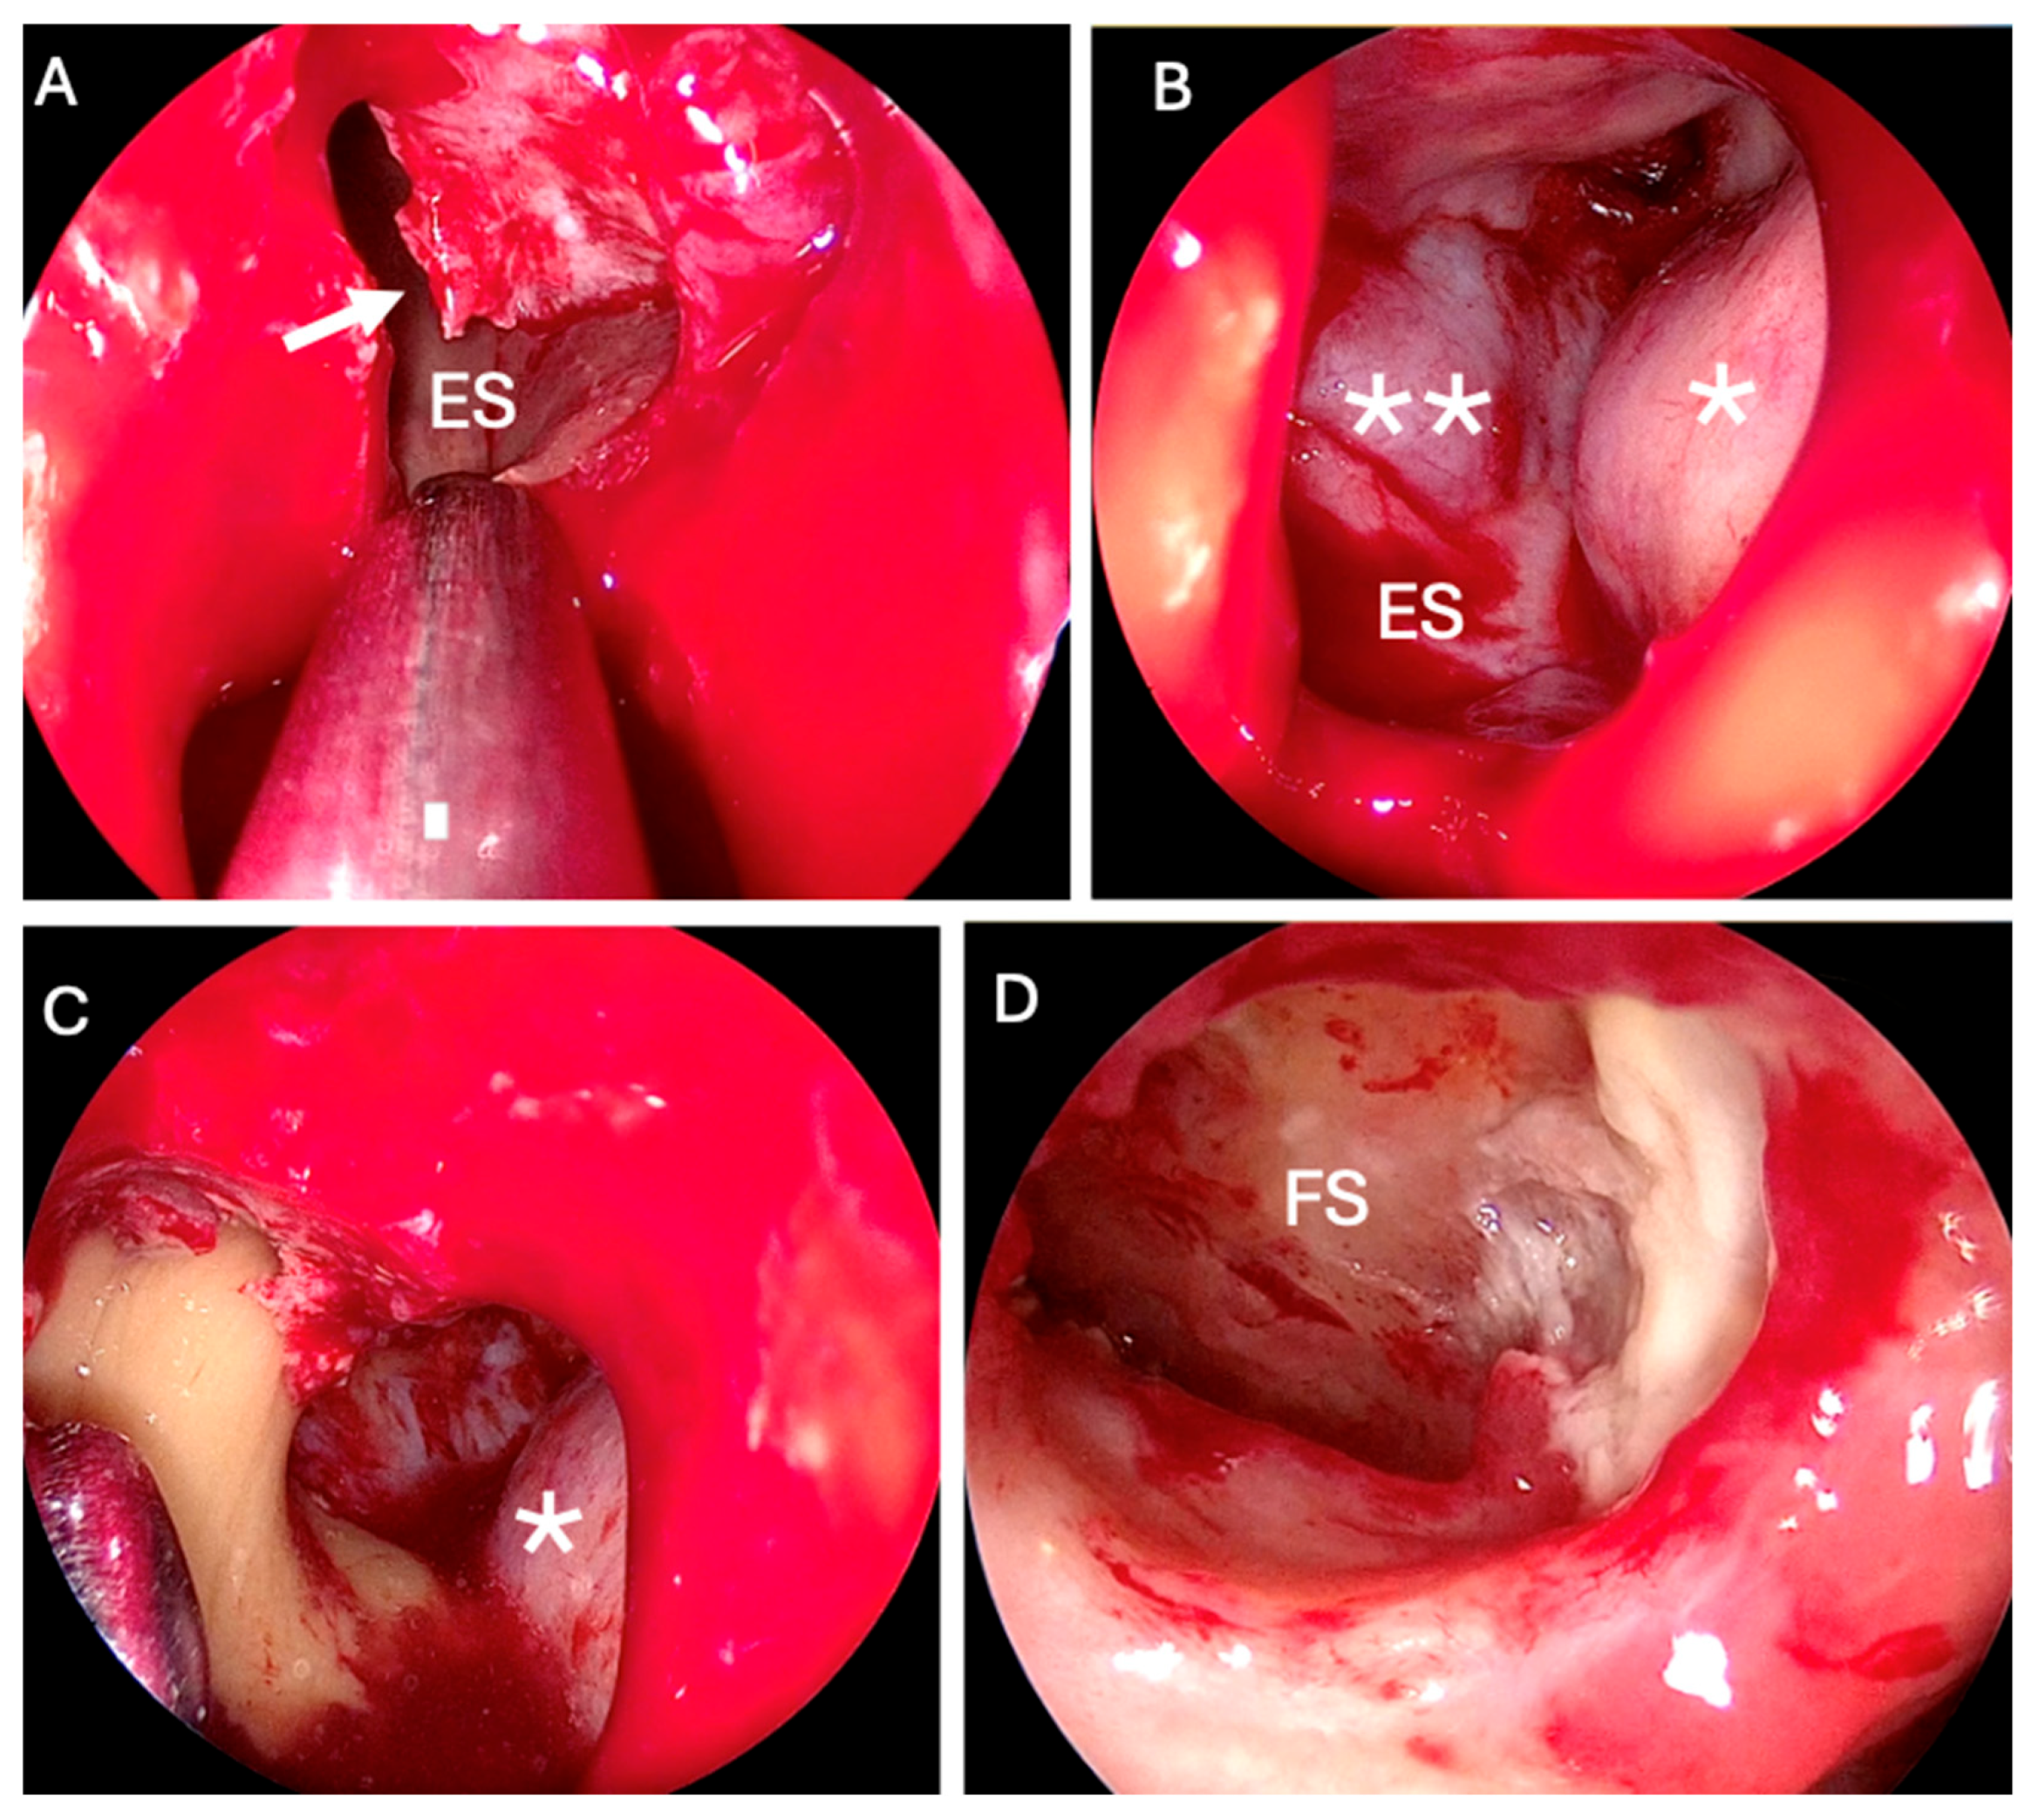

2. Case Report